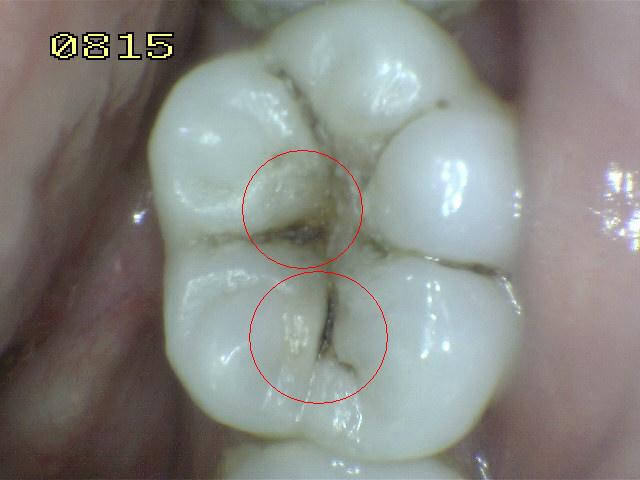

Código 3:

Ruptura localizada del esmalte debido a caries sin dentina visible

- El diente visto en estado

húmedo pueden tener una clara opacidad de caries (lesión de

mancha blanca)

y / o decoloración marrón de caries que es más ancha que la

fisura natural y la fosa, que no es consistente con la

apariencia clínica de esmalte sano. Una vez seco, se

observa una pérdida de estructura dental cariada en la

entrada, o dentro de la fosa o fisura . Esto se ve

visualmente como evidencia de desmineralización en la

entrada o dentro de la fisura o fosa, y aunque la fosa o

fisura puede aparecer sustancialmente más ancha que lo

natural, la dentina no es visible en las paredes o la base

de la cavidad ó discontinuidad .

-

En caso de duda, o

para confirmar la evaluación visual, la sonda de la OMS /

IPC / PSR puede ser

utilizada con cuidado a través de la superficie del diente,

para confirmar la presencia de una cavidad ( < 0,5mm.de

profundidad) al parecer limitada al esmalte . La

identificación de la cavidad se consigue deslizando el

extremo de la bola a lo largo de la fosa o fisura

sospechosa.